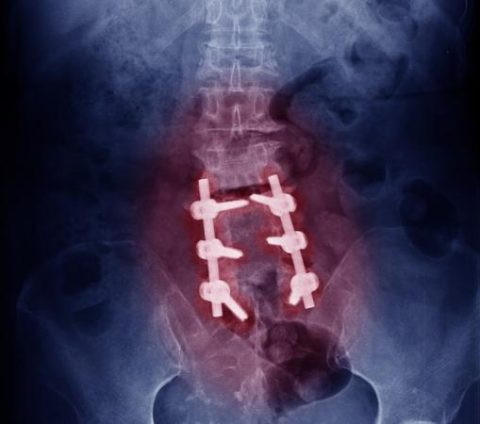

Metal plates, screws, or rods may be used to provide additional stability.